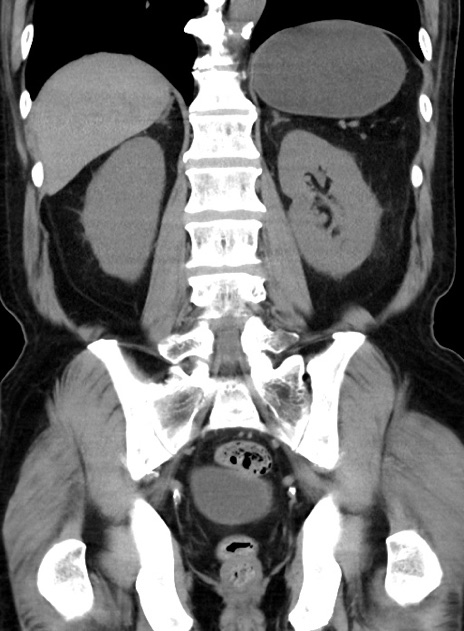

症例38(冠状断像)

【症例】70歳代 男性

【主訴】腹痛・嘔吐

【現病歴】昨晩より、嘔吐・腹痛あり。今朝になっても嘔吐あり。来院。

【既往歴】心臓バイパス手術、開腹胆摘、腸閉塞

【身体所見】BP 107/71mmHg、HR 116/min、腹部:平坦、軟、下腹部に軽度圧痛あり。反跳痛なし。

【データ】WBC 15100、CRP 0.32